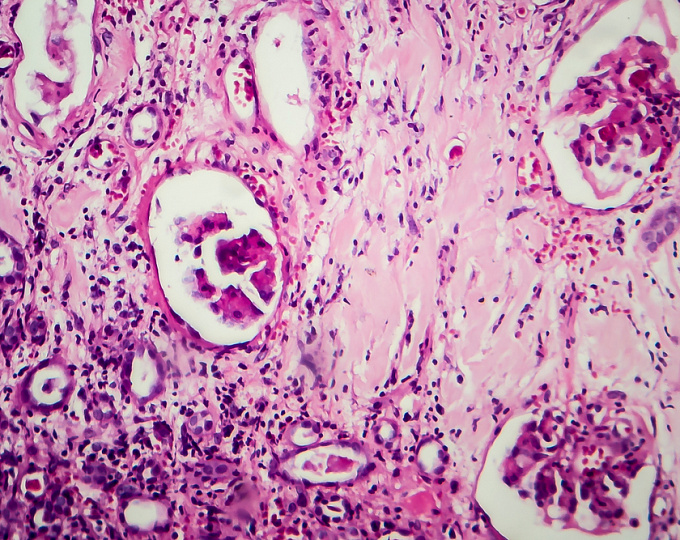

• Гломерулосклероз выступал независимым предиктором долгосрочного снижения почечной функции у пациентов с рецидивирующим волчаночным нефритом, но не у пациентов с впервые выявленным волчаночным нефритом.

Гломерулосклероз выступал независимым предиктором долгосрочного снижения почечной функции у пациентов с рецидивирующим волчаночным нефритом.